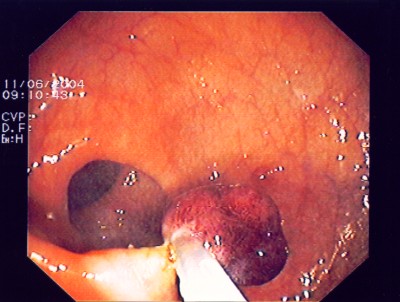

Großer Polyp des Dickdarmes